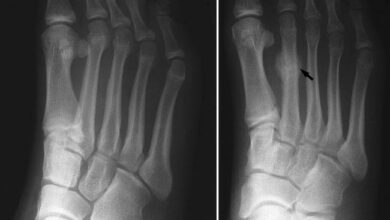

0 تا 100 ترکخوردگی تنشی دویدن | دلایل و پیشگیری از آن 🏃♀️

همه مصدومیتهای دویدن مثل هم ایجاد نمیشوند. در حالی که یک ترکخوردگی تنشی ممکن است بیضرر به نظر برسد، اما…